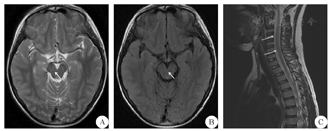

患儿 男,9岁,因"发热头痛5 d"于2019年3月8日入院。患儿母亲代诉患儿于入院前5 d无明显诱因出现发热、头痛,热型不规则,体温最高达38.9 ℃,头痛呈阵发性前额部疼痛,发热时明显,热退后疼痛稍缓解。于当地医院诊治后仍有反复发热,遂转至我院进一步治疗。患儿既往体质一般,否认特殊病史,个人史和家族史均无特殊,否认蚊虫叮咬、动物抓咬伤和传染性疾病接触史,生长发育状况与正常同龄儿童相仿。内科体检:体温36.4 ℃,脉搏95次/min,呼吸频率22次/min,血压95/58 mmHg(1 mmHg=0.133 kPa),咽红,咽峡部未见明显疱疹,双侧扁桃体Ⅱ度肿大,心肺腹无异常,手足无皮疹,双下肢无水肿。神经系统体检:神志清楚,精神反应稍差,体检欠配合,双侧瞳孔等大等圆,对光反射灵敏,颅神经征(-);四肢肌力、肌张力及浅感觉均正常,四肢反射对称,腱反射(++),颈抗阳性,双侧Kernig征、Brudzinski征阴性,病理征未引出。辅助检查:血常规示单核细胞比例增高(14.6%,正常值3.0%~10.0%)。电解质示钾离子减低(3.05 mmol/L,正常值3.50~5.30 mmol/L)、钠离子减低(132.1 mmol/L,正常值135.0~145.0 mmol/L)。大小便常规、肝肾功能、心肌酶、C反应蛋白、血沉、术前抗体三项均大致正常,呼吸道病毒七联检均阴性。腰椎穿刺脑脊液常规检查示其外观无色、透明,压力未测,白细胞计数增高[220×106/L,正常值(0~10)×106/L],单个核细胞比例增高达99%;脑脊液细胞学检查示白细胞计数高度增高(213.0×106/L),以淋巴细胞为主;脑脊液生化示蛋白水平升高(1562 mg/L,正常值150~450 mg/L),其余糖、氯化物水平均正常。颅脑及脊髓MRI增强扫描示双侧大脑半球及脑干表面柔脑膜稍增厚强化,C2~T11椎体水平脊髓内异常信号,增强后可见强化,部分脊膜及双侧脊神经强化,并可见脑干异常信号(图1)。对患儿予以抗感染、脱水等对症支持处理,1周后患儿逐渐出现胡言乱语、意识障碍及大小便障碍,双上肢肌力下降至4级,右下肢肌力下降至3级,左下肢肌力下降至2级。复查腰穿脑脊液结果较上次变化不大,脑脊液及血清抗水通道蛋白4(AQP4)、髓鞘碱性蛋白(MBP)、髓鞘少突胶质细胞糖蛋白(MOG)抗体阴性;脑脊液及血清N-甲基-D-天冬氨酸受体(NMDAR)型抗体、α-氨基-3-羟基-5-甲基-4-异恶唑丙酸(AMPA)1型抗体、AMPA2型抗体、抗富亮氨酸胶质瘤失活蛋白抗体、抗接触蛋白关联蛋白2(CASPR2)、抗γ-氨基丁酸B型(GABAB)受体抗体IgG阴性;脑脊液病原微生物高通量基因检测发现EBV,诊断为EBV感染性脑膜脑脊髓炎。对患儿予以加用阿昔洛韦抗病毒、大剂量甲强龙冲击治疗以及脱水、维持水电解质平衡等对症支持处理,患儿症状高峰期持续4 d后病情逐渐好转,1个月后基本恢复正常,仅遗留双下肢肌力稍差(4级)。9个月后复查患儿头颅及脊髓MRI,示恢复至正常(图2)。

A:T2WI示脑干弥漫性高信号消失;B:液体衰减反转恢复序列示脑干弥漫性高信号消失;C:T2WI示长节段脊髓病变消失;箭头所示为原病变处